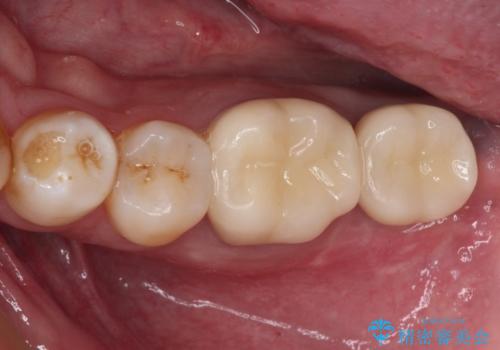

- 透明感がなく、歯肉ラインに歯根の色や金属が見えていることを気にして来院された患者様です。

装着されているメタルセラミックはなぜか連結されていましたが、1本ずつのオールセラミッククラウンへ変更することとしました。